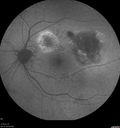

Polypiodal Choroidal Vasculopathy - Temporal Macula - Left eye

82 year old man with asymptomatic PCV in the left eye. Vision 20/50 OD, 20/32 OS did well with Lucentis

Polypoidal Choroidal Vasculopathy - ICG